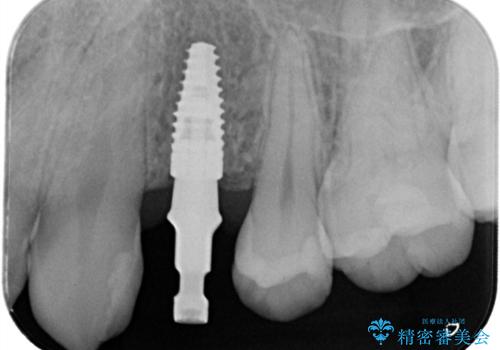

- 440,000円(インプラント体220,000円+カスタムアバットメント110,000円+オールセラミッククラウン110,000円)費用は治療当時の料金となります

長い間虫歯を放置していたため、根っこだけになっている状態でした。このままでは被せ物を被せられないため抜歯を行い治癒を待った後にインプラントを埋入しオールセラミッククラウンで治療を行いました。